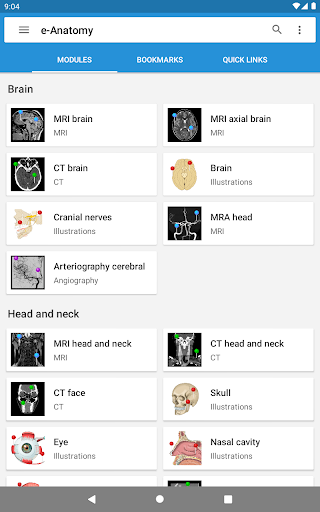

New : You can now filter the modules by region or by content type so you can find the module you are looking for much faster.

-Two new modules : Brain - TOF and Brain Angiography, Atlas of normal neurovascular anatomy of arteries of the brain on a cerebral angiogaphy.-The interface has been reworked.-A new tab named "QuickLinks" is available, dispatching modules in sections of the human body and allowing you to fast travel to the modules you are looking for.-Fixed small bugs.